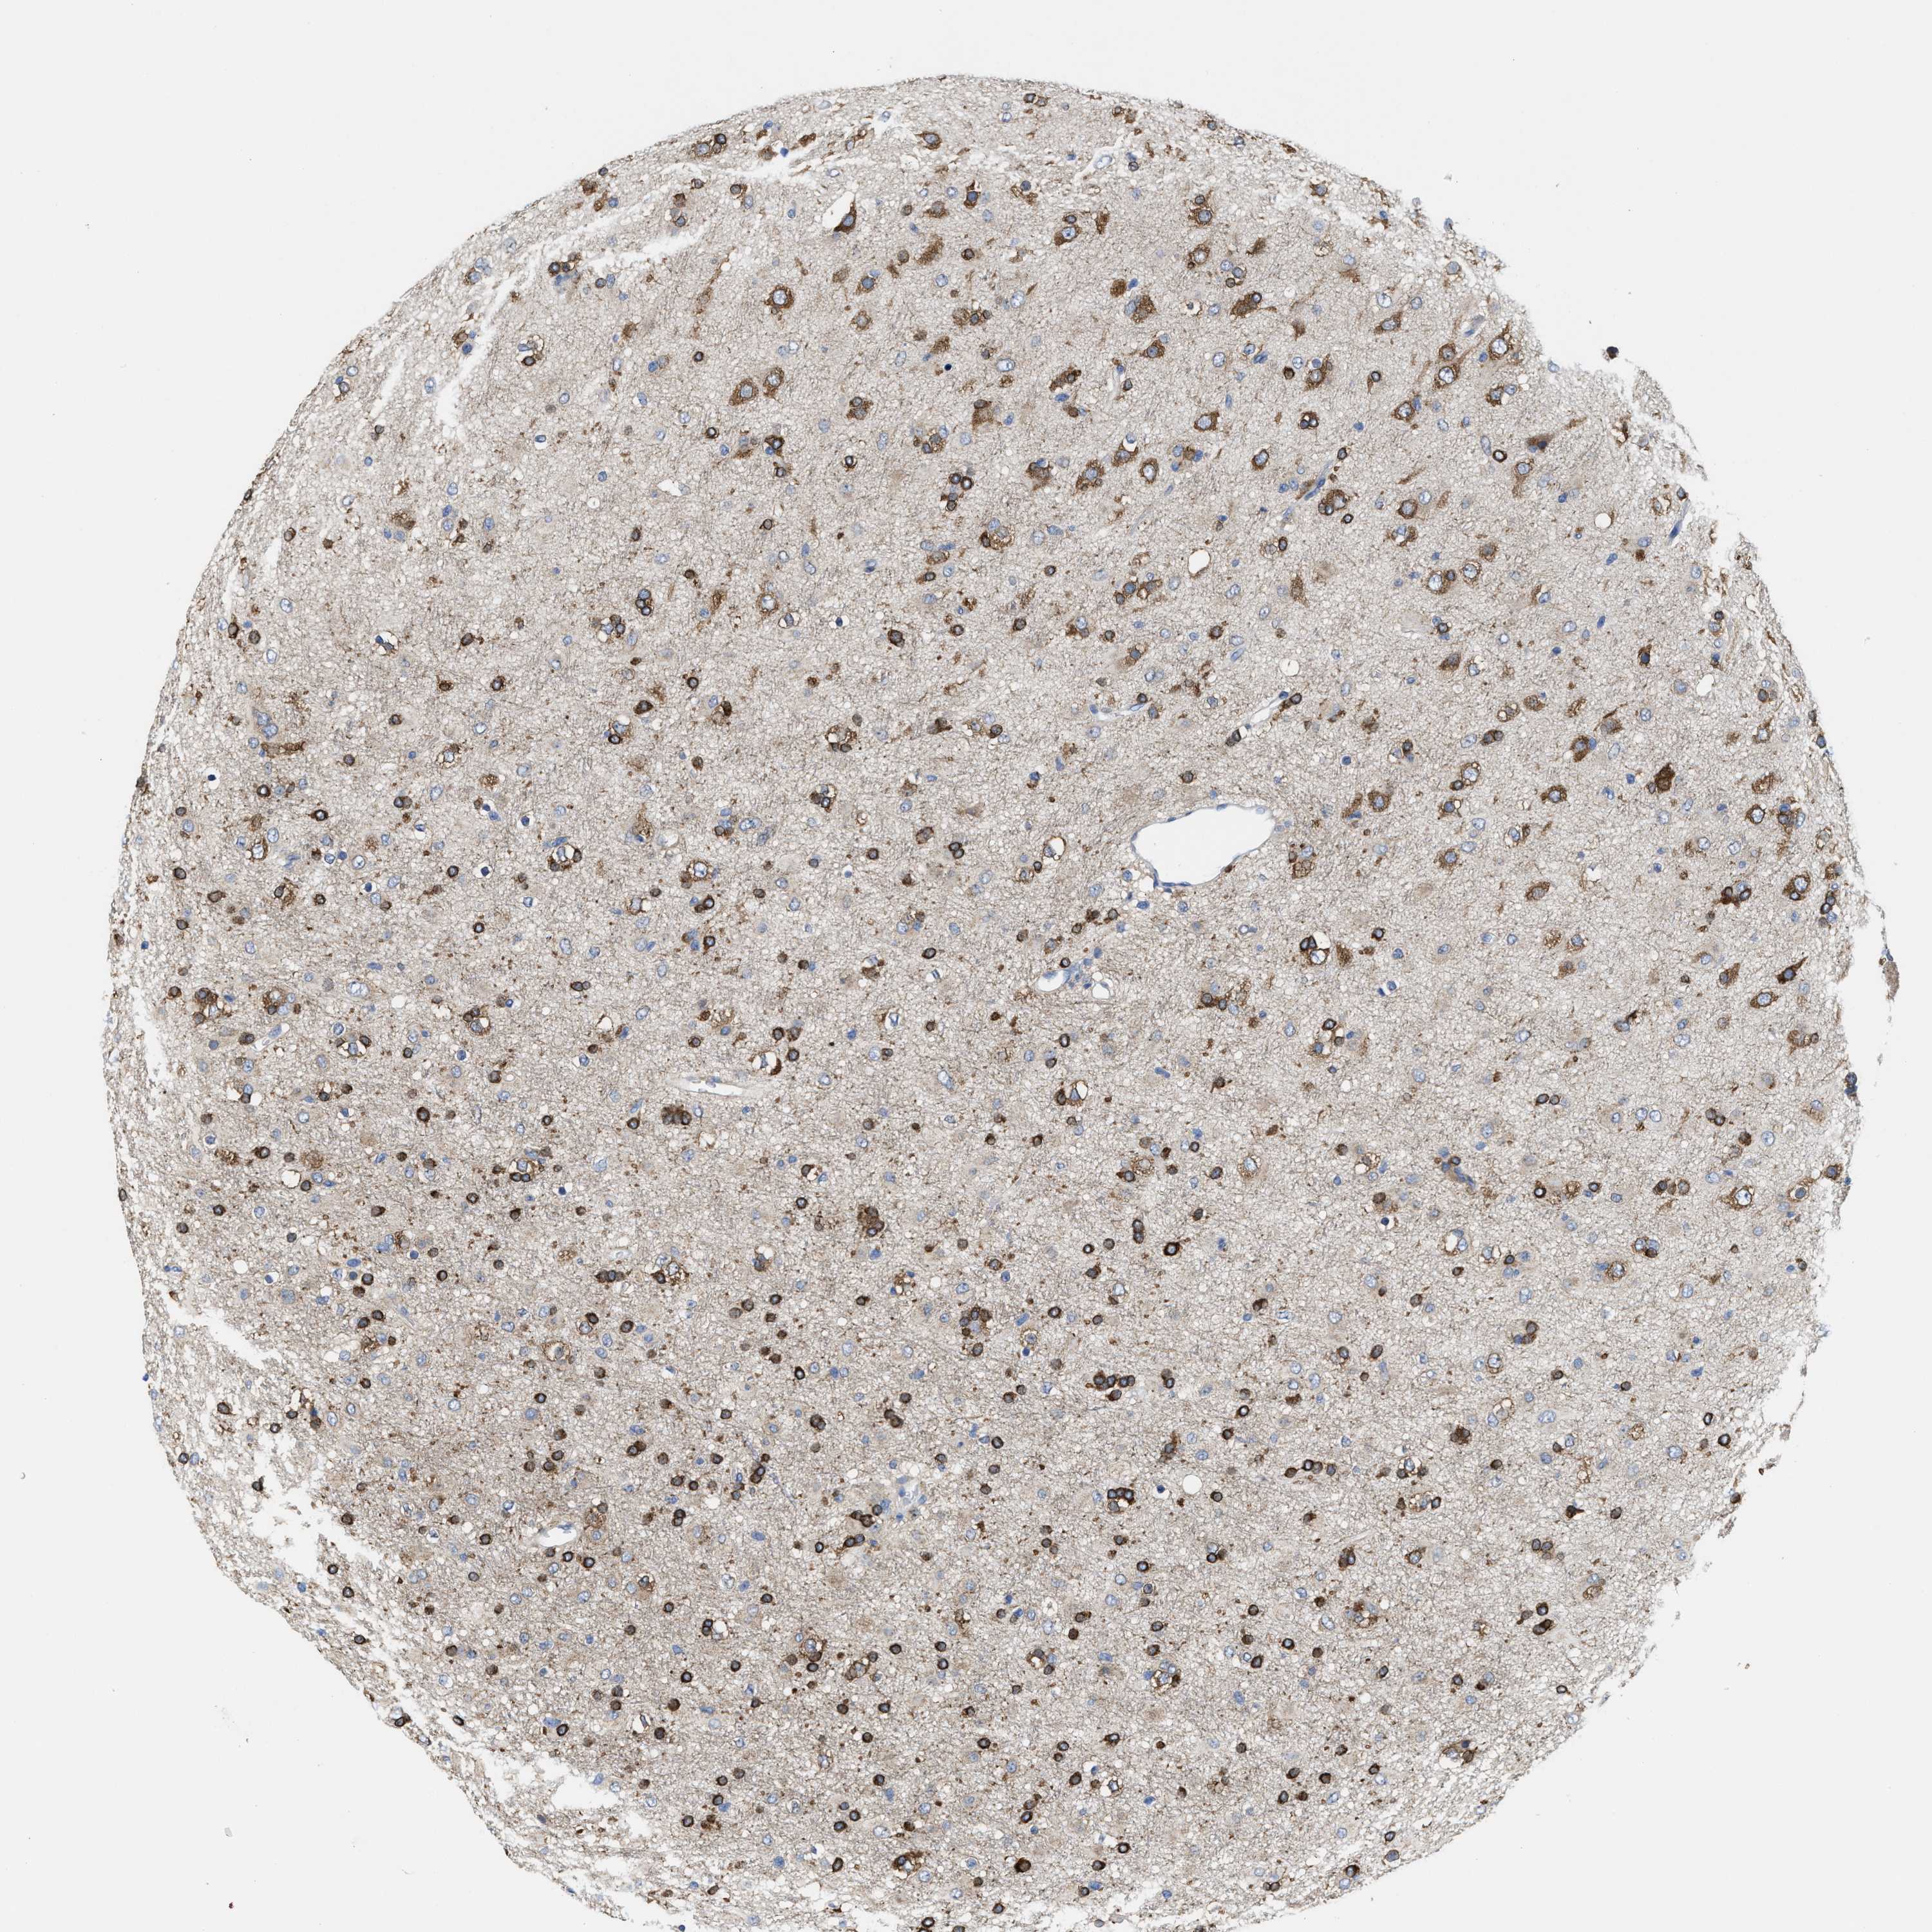

GLIOMA - Protein expressioni

A mouse-over function shows sample information and annotation data. Click on an image to view it in a full screen mode. Samples can be filtered based on level of antibody staining by selecting one or several of the following categories: high, medium, low and not detected. The assay and annotation is described here.

Note that samples used for immunohistochemistry by the Human Protein Atlas do not correspond to samples in the TCGA dataset.

Antibody stainingi

Antibody staining in the annotated cell types in the current human tissue is reported as not detected, low, medium, or high, based on conventional immunohistochemistry profiling in selected tissues. This score is based on the combination of the staining intensity and fraction of stained cells.

Each image is clickable and will lead to virtual microscopy that enables deeper exploration of all samples and also displays staining intensity scores, fraction scores and subcellular localization as well as patient and tissue information for each sample.

Antibody HPA019324

Staining

High

Medium

Low

Not detected

Intensity

Strong

Moderate

Weak

Negative

Quantity

>75%

75%-25%

<25%

None

Location

Nuclear

Cytoplasmic/membranous

Cytoplasmic/membranous,nuclear

Glioma, malignant, High grade

Glioma, malignant, Low grade